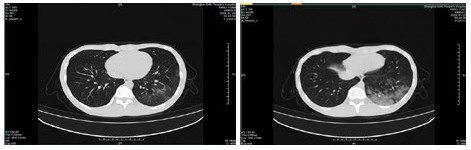

| 图 2 患者,女性,64岁,武汉籍,发病前1 d由武汉自驾车入沪,出现发热,体温39.9℃, 伴全身乏力,无咳嗽症状,无鼻塞,流涕症状,血白细胞总数及淋巴计数正常,甲乙型流感病毒筛查阴性,新型冠状病毒核酸检测阳性,肺部CT双肺多发磨玻璃结节,部分贴近胸膜,左肺有少量胸腔积液,局部小叶间隔增厚, 可见纤维条索影 Fig 2 Case 2, female, 64 years old, born in Wuhan. One day before the onset of the disease, she drove into Shanghai from Wuhan and had fever. Her body temperature was 39.9℃, with general asthenia, no cough, no nasal obstruction and running nose, normal WBC and lymphoid count, negative influenza A and B virus screening, positive novel coronavirus nucleic acid test. Lung CT showed multiple ground glass nodules, some of which were close to pleura, a small amount of pleural effusion in the left lung, and local interlobular septa was thickened, with visible fibrous streak shadow |

| 图 3 患者,女性,49岁,沪籍,发热10 d,体温最高38.5℃,伴乏力,肌肉酸痛,既往体健。否认武汉流行病学接触史,有菜场买菜史。血白细胞总数及淋巴计数正常,甲型、乙型流感筛查阴性,新型冠状病毒核酸检测阳性。肺部CT提示双肺磨玻璃结节,可见血管充血,增粗,穿行,部分贴近胸膜,伴小叶间隔增厚 Fig 3 Case 3, female, 49 years old, born in Shanghai, had fever for 10 days, body temperature 38.5℃, with fatigue, muscle pain, previous physical fitness. She denied the history of epidemic exposure of Wuhan, but had the history of shopping in market. Normal WBC and lymphoid count, negative influenza A and B virus screening, positive novel coronavirus nucleic acid test. Lung CT showed bilateral ground glass nodules with hyperemia, thickening and passage of blood vessels. Some were close to pleura with thickening of interlobular septum |